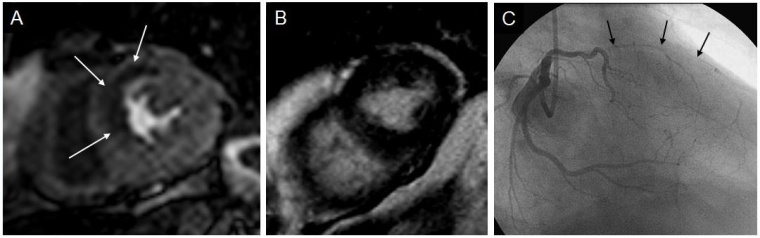

Bei Patienten mit akutem Herzinfarkt kann die Kardio-MRT wichtige Daten zur Risikostratifizierung und Prognoseabschätzung liefern. Auch wenn schon einmal ein Herzinfarkt überlebt wurde, kann im weiteren Verlauf eine pharmakologische Belastungsuntersuchung zum Ausschluss einer Gefährdung durch ischämierelevante Verengungen (Stenosen) der Herzkranzgefäße erfolgen. Mehrere unabhängige Studien konnten bei unauffälligen Untersuchungen, d. h. Befunden ohne neue Durchblutungsstörungen, einen unbeeinträchtigten Verlauf nachweisen.

Insbesondere bei jüngeren Patienten kann bei ähnlichen Beschwerden mithilfe des Kardio-MRT nicht nur eine Herzmuskelentzündung von einem akuten Herzinfarkt, sondern auch zwischen akuter und abgelaufener Herzmuskelentzündung unterschieden werden. Da die Methode ohne Röntgenstrahlung arbeitet, können problemlos Verlaufsuntersuchungen zur Therapiekontrolle durchgeführt werden.